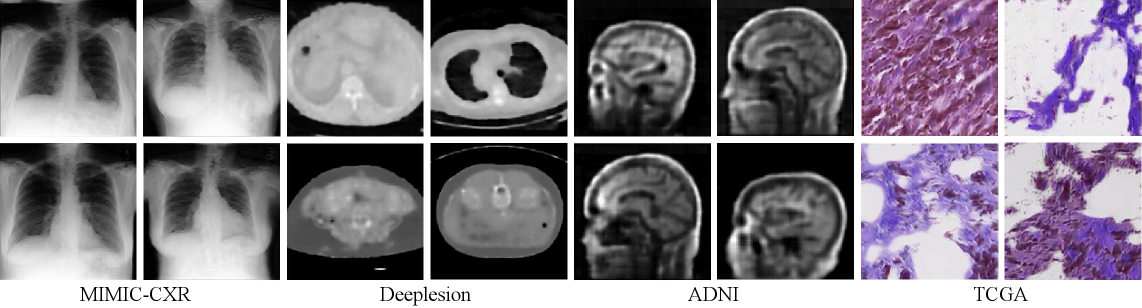

Figure 3: Visualizations of synthetic data generated by our inversion-driven framework, showcasing its versatility across diverse medical tasks. The figure displays samples from four imaging modalities (two columns each): X-ray, CT, MR, and Pathological imaging.

Datasets. We follow the experimental setup and dataset selection from MedCoSS [51], utilizing a large-scale multi-modal pre-training corpus and evaluating on a diverse set of nine downstream benchmarks. The pre-training corpus is assembled from five unlabeled public datasets across distinct medical modalities: 1D clinical reports and 2D chest radiographs from MIMIC-CXR [19], 3D CT scans from DeepLesion [48], 3D MRI scans from the ADNI database [18], and histopathology images from 7 The Cancer Genome Atlas (TCGA) projects: TCGA-THYM, TCGA-THCA, TCGA-BRCA, TCGA-UCEC, TCGA-UVM, TCGA-OV, TCGA-MESO. Considering our model inversion method is designed for image modality, we keep the same real text buffer for fair comparison with MedCoSS [51]. We evaluate our model on nine downstream benchmarks across five modalities: report classification on PubMed20k [6]; X-ray analysis with COVID-19 classification on ChestXR [1] and lesion segmentation on QaTa-COV19-v2 [5]; CT analysis via COVID-19 classification on RICORD [39] and liver and tumor segmentation on LiTS [2]; MRI segmentation on Vestibular Schwannoma (VS) [33] and Left Atrium (LA) [47] datasets; and pathology analysis using NCH [20] and GlaS [34] for tissue classification and gland segmentation, respectively. All data splits and pre-processing follow MedCoSS [51]. Further dataset details are provided in Appendix A.

Qualitative Analysis. Fig. 3 visualizes synthetic data generated across four medical imaging modalities. The inverted images exhibit anatomically plausible structures across X-ray, CT, MRI, and pathological imaging. While the synthetic samples lack fine-grained textural details and sharpness compared to real medical images, they successfully capture essential anatomical morphology and modality-specific characteristics. The strong downstream performance, including segmentation tasks detailed in the Appendix D.1, validates that such structurally coherent synthetic data, despite missing low-level details, is highly competent for knowledge retention in CL. This confirms that preserving core semantic and structural information is more critical than pixel-level fidelity for effective knowledge transfer in SSL. More synthetic examples are provided in the supplementary material.